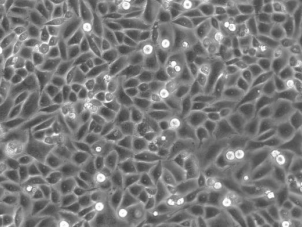

SiHa细胞是建自一个日本病人的外科手术的原位组织样品。电镜观察表明,在SiHa细胞连接处有典型的桥粒,在SiHa细胞胞质中有丰富的张力丝。在裸鼠中,SiHa细胞能形成低分化的表皮样癌(Ⅲ级);SiHa细胞中,癌基因PRB和p53阳性。

细胞形态 上皮细胞样

生长特性 贴壁生长